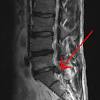

L'opération d'une hernie discale fait parfois peur et de nombreuses personnes refusent de se faire opérer. Hernia de disc, cunoscuta si sub numele de ruptura a discului intervertebral, este o afectiune prin care o parte din discul intervertebral apasa elementele anatomice din canalul spinal (radacinile nervoase si maduva spinarii). Hernia de disc poate fi operata, insa nu trebuie operata, decat in cazuri bine argumentate!

Hernia de disc apare prin prolabarea nucleului pulpos prin fisurile inelului fibros ale discului degenerat spre ligamentul longitudinal posterior astfel:

Hernia de disc este o conditie care apare de obicei din cauza propriei noastre neatentii sau neglijente. Clasificarea și fazele herniei de disc. Hernia de disc apare dacă discul se fragmentează și ajunge să comprime rădăcinile nervoase sau măduva spinării aflate în canalul spinal din vecinatatea sa.

Hernia de disc poate apare în orice regiune a coloanei vertebrale, dar este cel mai adesea localizată la nivel lombar. Hernia de disc este o afectiune neurologica si apare atunci cand unul dintre discurile coloanei vertebrale se deplaseaza. Ce este hernia de disc?